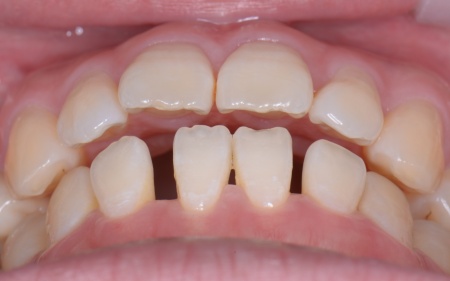

また、上下の歯を噛み合わせた際に前歯が噛み合わず隙間ができる開咬(かいこう)と呼ばれる噛み合わせも見られました。

開咬は奥歯に負担が集中しやすく、その影響で今回のように歯の根が割れてしまった可能性が高いと考えられます。

治療終了後、下前歯の間に見られる三角形のすき間(ブラックトライアングル)が気になるとのご相談がありました。

そこで、歯の表面に白いプラスチック樹脂を直接盛り付けて形を整えるダイレクトボンディングを行い、すき間が目立ちにくいよう調整して、治療を終了しました。